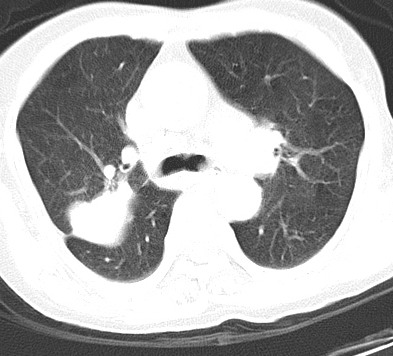

以下是引用hhcckk在2007-3-2 14:51:00的发言:[br]考虑结核球可能性大,依据[br]1病灶在下叶背段,结核的好发部位[br]2病灶内有大量的钙化,纵隔内有大量的淋巴结钙化[br]3重要的是半年前与现在相比无变化,假如是肿瘤的话不会这么‘善良’[br]4病灶周围卫星灶不明显,病灶有毛刺,胸膜凹陷,肿瘤不能完全排除,有条件的话最好做个活检

以下是引用liuyue在2007-3-2 17:15:00的发言:[br]1位置:右上叶后段[br]2性质:大分叶、粗长毛刺、条状斑片状钙化、纵隔多发淋巴结钙化,无强化,故考虑:肺结核灶(陈旧)